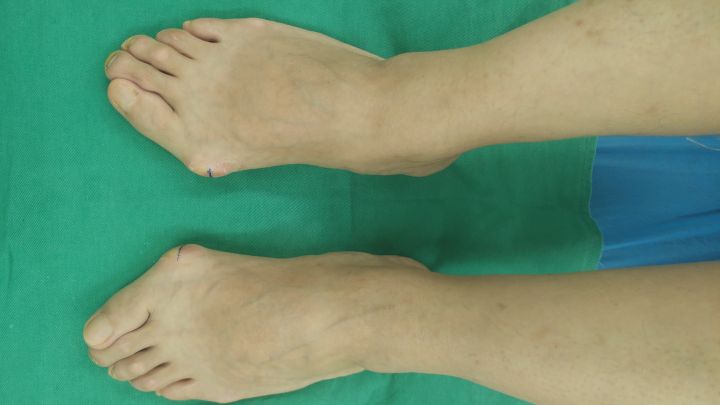

拇外翻-已拇趾向外侧偏斜,伴有局部凸起

痛风-第一跖趾关节周围凸起,拇趾不太偏斜

痛风凸起,多伴有偶尔剧烈疼痛